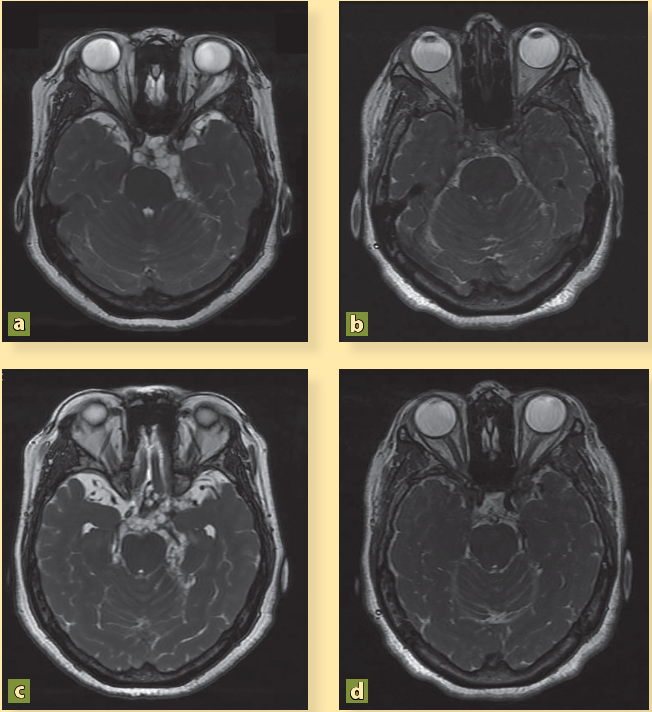

La paciente presenta mejoría clínica y es egresada por remisión de la cefalea y de las crisis convulsivas tras 16 días de estancia hospitalaria con indicaciones de continuar con esteroides vía oral y fármacos anticomiciales. Por iniciativa propia, la paciente no acudió a sus citas de seguimiento durante 4 años. Después, y debido a que ha presentado cefalea con intensidad 10/10, náusea y vómito constantes, desorientación y alteraciones del lenguaje, y varios episodios convulsivos, es traída por sus familiares al servicio de urgencias. Los familiares informaron que el tratamiento médico fue abandonado y optaron por una terapia de medicina naturista. Se ingresó la paciente y la nueva RM mostró persistencia de los cisticercos (figuras 2A, 2C, 3A, 4A) así como dilatación de los ventrículos (figura 5A). Se colocó una derivación ventrículo peritoneal (DVP) (figura 5B) y se inició nuevo tratamiento con albendazol (15 mg/kg), praziquantel (50 mg/kg) por 10 días, y dexametasona (8 mg/8h). Tras 40 días de estancia hospitalaria, se decidió su egreso con cita en la consulta externa.

En a y c se observan imágenes quísticas a nivel del espacio subaracnoideo adyacente al giro temporal superior y en la cisterna pontina, compatibles con NCC, mientras que en b y d han desaparecido después del tratamiento con albendazol.

Figura 2 Resonancia magnética secuencia FIESTA

El resultado del tratamiento fue parcial y la paciente requirió de 8 ciclos de albendazol para poder inactivar la NCC. En la RM de 2019 se mostró la remisión total de los parásitos y la ausencia de hidrocefalia (figuras 2B, 2D, 3B, 4B). Actualmente la paciente se mantiene estable, sin cefaleas, ni eventos convulsivos y con un buen funcionamiento de la DVP.